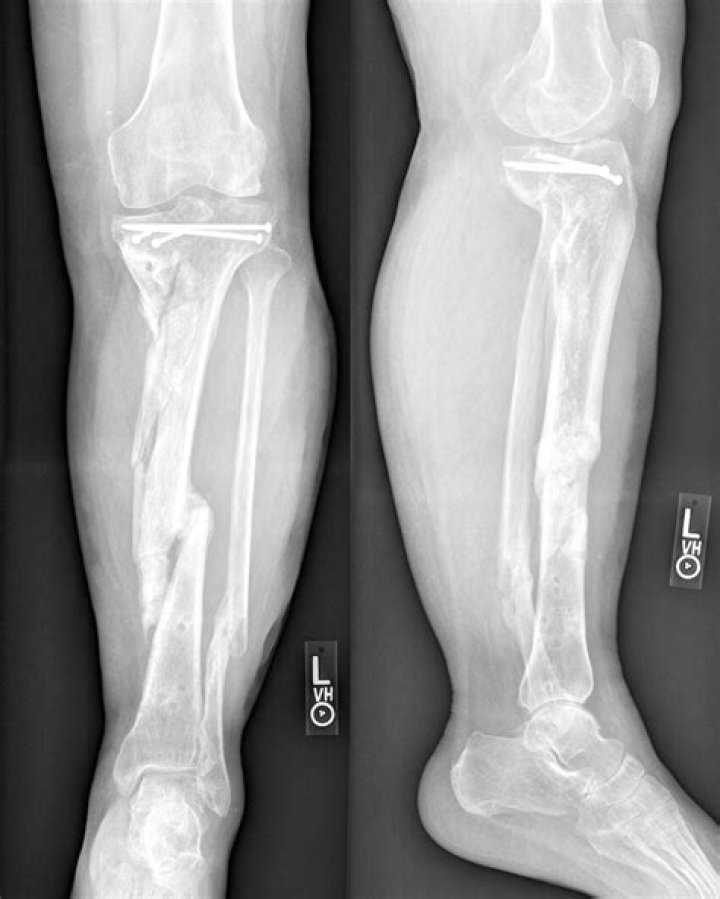

Georginio Wijnaldum At Risk Of Missing World Cup After Suffering Fractured Tibia

New Roma marking Georginio Wijnaldum is set for a lengthy spell uninvolved ensuing to breaking his tibia during an informative gathering. The Dutch midfie...